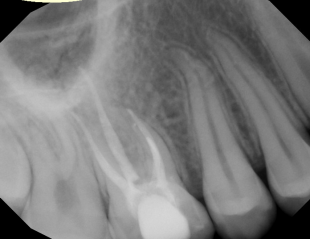

#30 NS-ReTx

Dx: Previously Treated with SAP